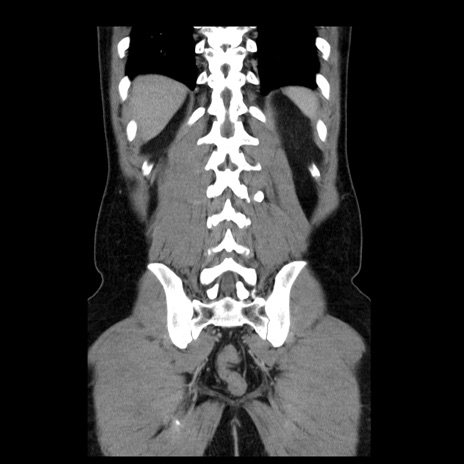

症例4(冠状断像)

【症例】30歳代男性

【主訴】腹痛、嘔吐

【現病歴】昨晩から突然の腹痛あり、その後嘔吐、軟便も出現。腹痛が改善しないため救急搬送となる。2日前にしめ鯖の食事歴あり。

【身体所見】意識清明、苦悶様、BP 135/90mmHg、BT 35.7℃、腹部:平坦、やや硬、心窩部〜臍部に自発痛、圧痛あり、筋性防御+、反跳痛-

【データ】WBC 8100、CRP 0.57